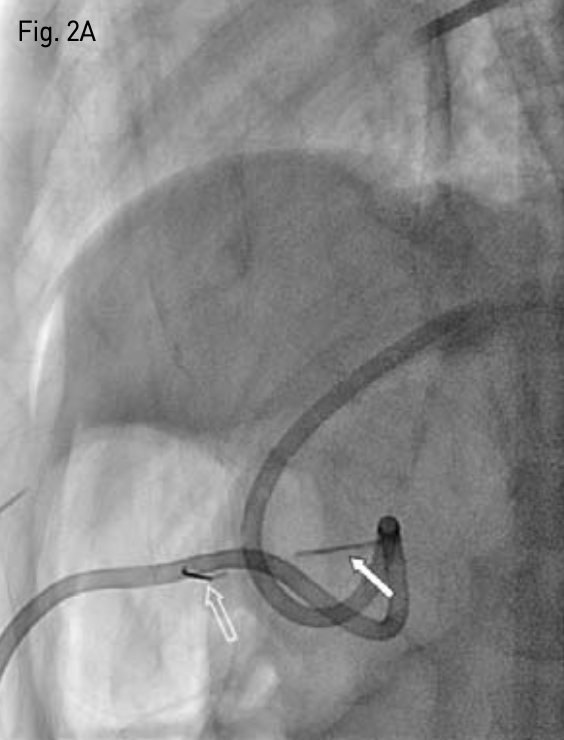

이후 기복증은 교정되었고(Fig. 3), 시술 1주일 후 마비성 장폐색도 좋아져 정상 퇴원하였음.

Fig. 3

Follow-up upright abdomen roentgenogram, obtained 1 week after T-fastener re-fixation shows dis appearance of pneumoperitoneum and improvement of paralytic ileus.